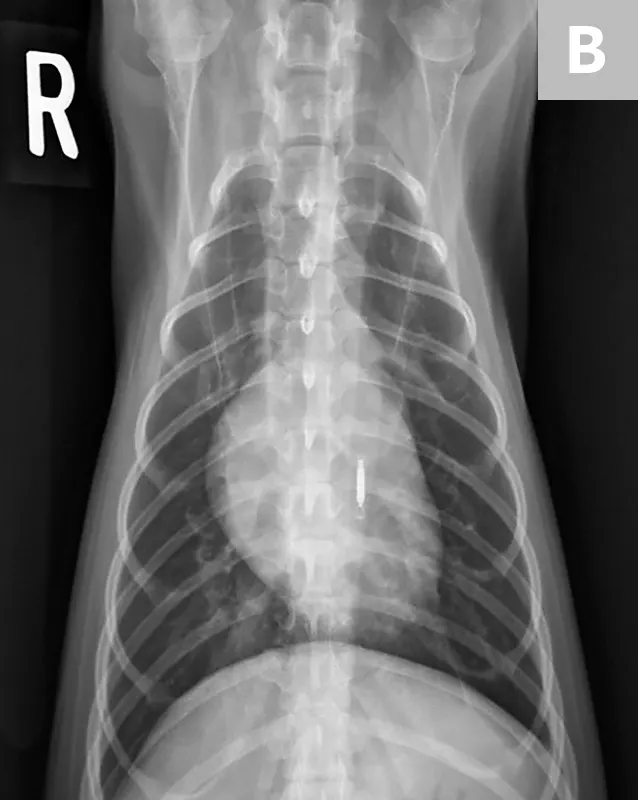

• Place the patient in dorsal recumbency for the ventrodorsal view. For ease in positioning, a V-trough helps keep the spine and sternum aligned and is more comfortable for the patient. With the head straight, tie the thoracic limbs cranially and the pelvic limbs caudally. Place a thin sandbag across the neck or on either side of the head if help is needed with restraint and positioning. The head and neck need to be straight, not turned to the side. (See Figure 4.)

• Make sure the sternum and dorsum are superimposed on the radiograph. If the spinous processes are visible pointing to one side, move the sternum in the direction they are pointing to straighten the spine and sternum. (See Figure 5.)